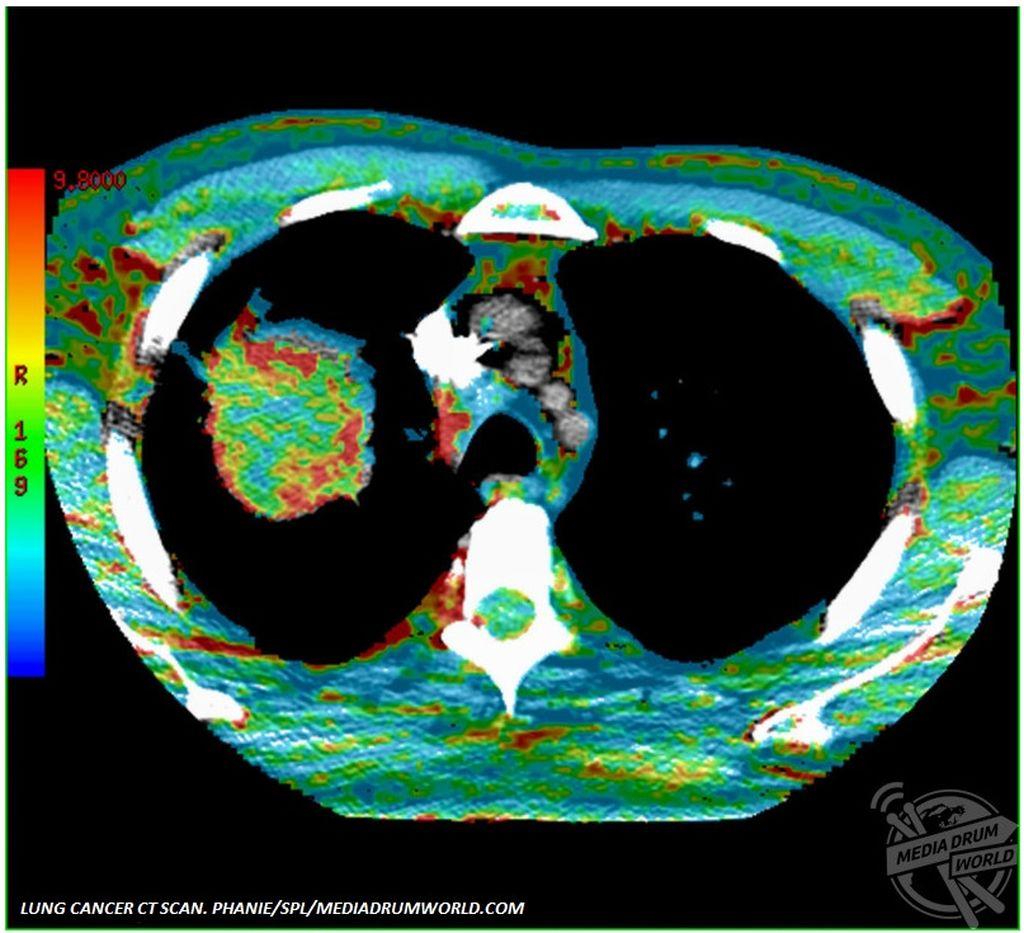

Μερικές από τις σοβαρότερες και πιο επίπονες ασθένειες που δυστυχώς αντιμετωπίζουν πολλοί άνθρωποι, αποτυπώνονται μέσα από φωτογραφίες έγχρωμες. Ασθένειες όπως ο καρκίνος και η αρθρίτιδα γίνονται φωτογραφίες και παίρνουν μορφή.

Από μια ακτινογραφία των δαχτύλων ασθενούς με αρθρίτιδα μέχρι έναν υπέρηχο ενός διογκωμένου προστάτη, οι φωτογραφίες παρουσιάζουν ασθένειες που πλήττουν χιλιάδες ανθρώπους ανά τον κόσμο, προκαλώντας έντονο πόνο και σημαντικούς περιορισμούς στην καθημερινότητα.